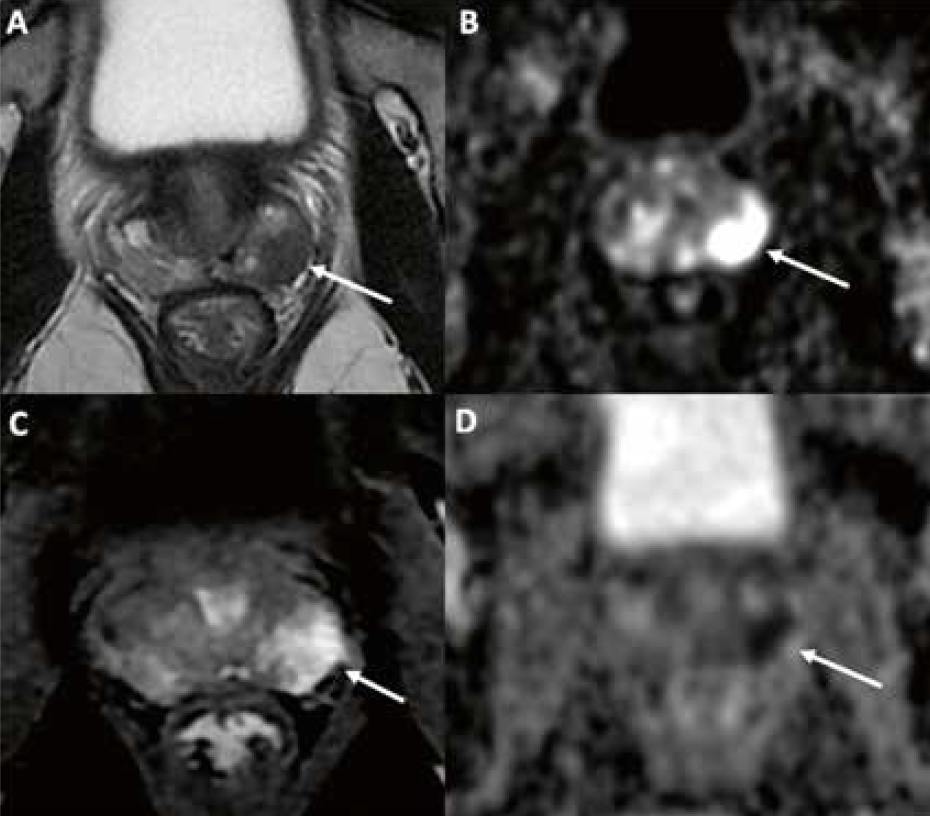

L’analyse de l’imagerie par un radiologue expérimenté permet ainsi de donner le score PI-RADS dans chaque zone prostatique. La présomption de malignité a été évaluée sur une échelle de 1 à 5 selon le score de Likert (score 1 : cancer très peu probable à score 5 : cancer très probable). Le PI-RADS est maintenant largement utilisé et validé, dans la pratique quotidienne et dans les études, par tous les praticiens impliqués dans la prise en charge du CaP. La figure 2 montre un exemple de cancer de la prostate de la zone périphérique gauche PI-RADS 5.

Figure 2 – IRM prostatique PI-RADS 5.

Patient de 66 ans avec un PSA à 12 ng/ml. Anomalie focale de la zone périphérique gauche de 16 mm à la partie moyenne avec effacement et irrégularité capsulaire, en hyposignal T2 (A, flèche), franc hypersignal diffusion (B, flèche), hyposignal ADC (D, flèche), et prise de contraste précoce (C, flèche). Gleason 4+3 sur les biopsies ciblées. Stade T3a IRM.